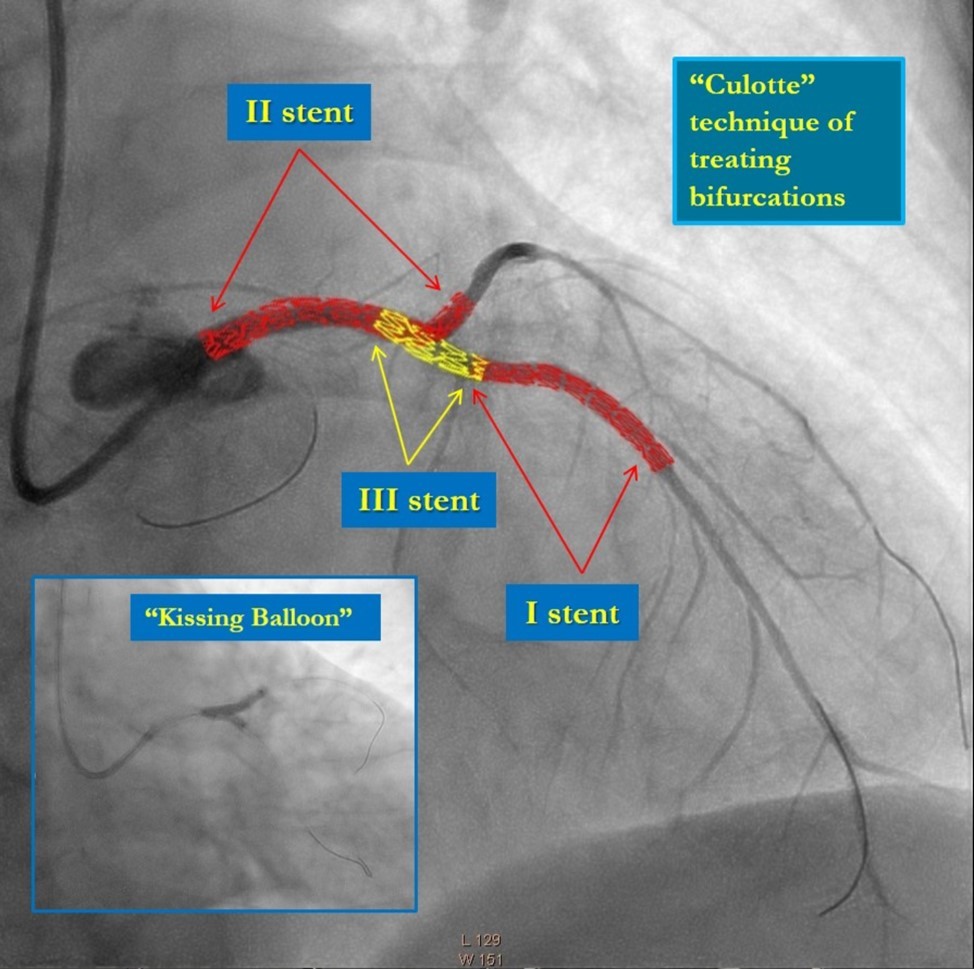

In the first stage, occluded left main and circumflex arteries were recanalized utilizing the support-balloon technique, and CTO wires (Miracle 3™ wire, Abbott Vascular; Runthrough® NS Intermediate wire, Terumo) and balloon pre dilatation was done (Figure 3). In the second stage, the occluded LAD artery was successfully recanalized by utilizing the support-balloon technique, and CTO wires (Figure 3) (due to severe calcinosis the second stage lasted 40 min). In the third stage, LAD artery, CX artery, as well as LMCA and its bifurcation, were stented with 3 drug-eluting stents (Resolute Integrity Zotarolimus DES, Medtronic), the "Culotte Stenting " technique was used for bifurcation stenting (Figure 4), followed by "Kissing Balloon" post-dilatation technique, and finally, proximal optimization technique was performed in the LMCA. The final angiographic image is good, the intervention ended without complications (Figure 5).

Figure 4.Culotte stenting technique